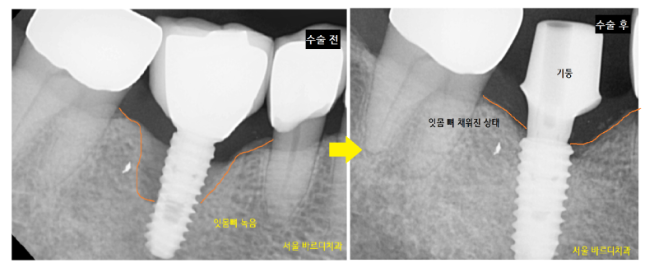

임플란트 염증으로 잇몸뼈가 많이 녹았습니다.

4년 전과 비교해 보면 잇몸뼈가 더 많이 녹은 것이

보이실 겁니다.

기존에 타 병원에서 식립했던 임플란트를 제거 후

재수술

그러니까 임플란트 교체하기로 상담해 드렸습니다.

기존에 문제를 일으킨 임플란트를 제거 후

새로운 제품으로 교체

녹은 잇몸 뼈는 뼈이식을 통해 해결했습니다.

230116~230613

수술 전후 녹았던 잇몸뼈가

임플란트 쪽까지 채워진 거 보이시죠~??